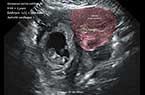

Grossesse môlaire volumineuse de 739 ml de volume Grossesse môlaire volumineuse de 739 ml de volume Grossesse môlaire volumineuse de 739 ml de volume